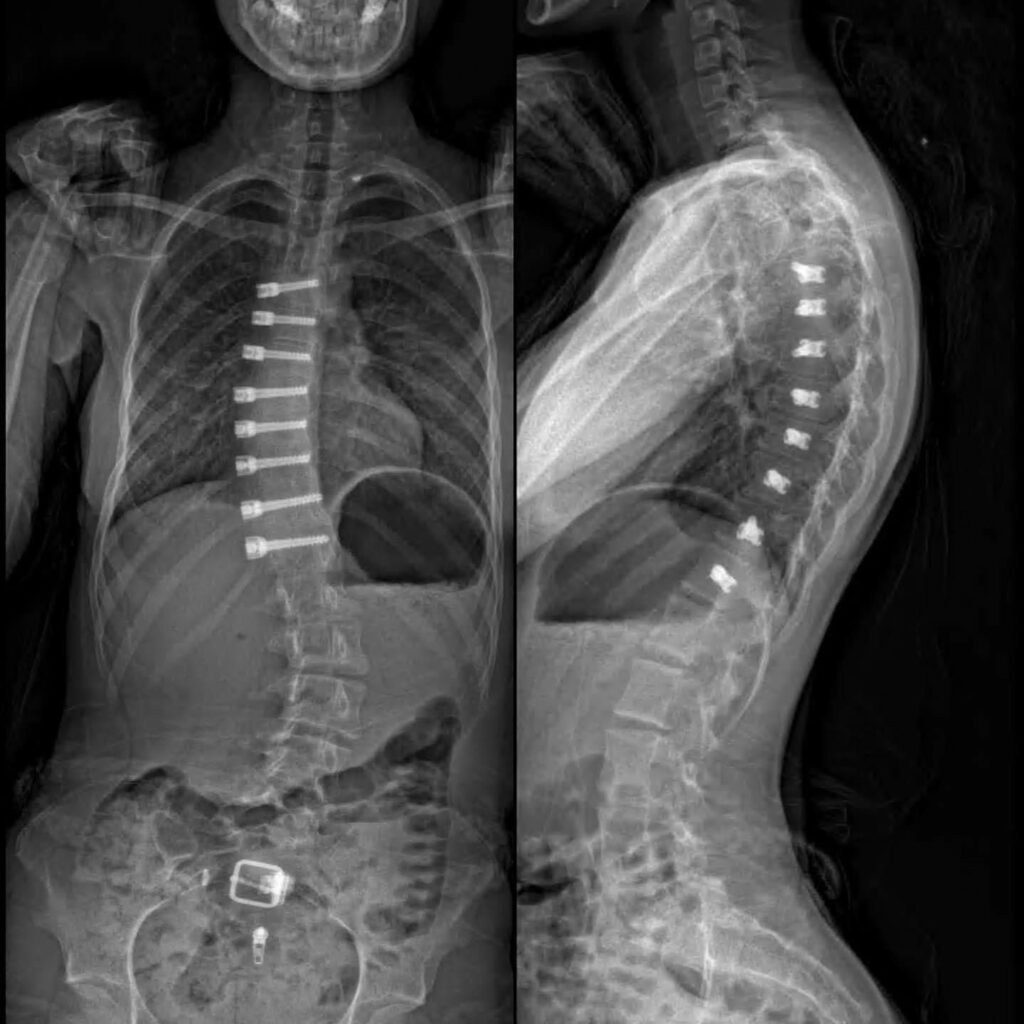

The procedure involves implanting a flexible, strong cord (the "tether") along the convex (outer) side of the spinal curve. This tether acts as a guide, slowing down growth on that side of the spine. As the child or adolescent continues to grow, the concave (inner) side of the curve catches up, leading to a gradual straightening of the spine.

A thorough evaluation by a qualified and experienced spine surgeon is crucial to determine if tethering is the right option for a particular patient. This evaluation will include a physical examination, X-rays, and potentially other imaging studies to assess the degree and flexibility of the curve, as well as the patient's skeletal maturity.

- The Surgery: The procedure is typically performed under general anesthesia and involves placing the tether along the spine using minimally invasive techniques.